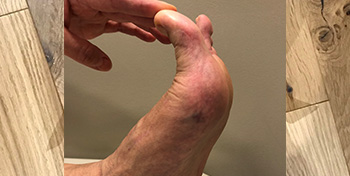

- Ganglion located on the side of the ankle, causing much discomfort during hikes or when wearing ski boots. US aspiration had been unable to fully drain it.